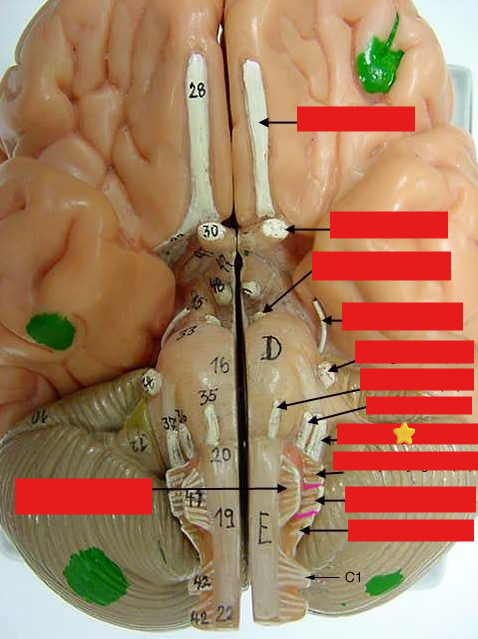

cranial nerves

12 Terms

1

olfactory

2

optic

3

oculomotor

4

trochlear

5

trigeminal

6

abucens

New cards

7

facial

8

vestibulocochlear

New cards

9

glossopharyngeal

New cards

10

vagus

New cards

11

accessory

New cards

12

hypoglossal

New cards